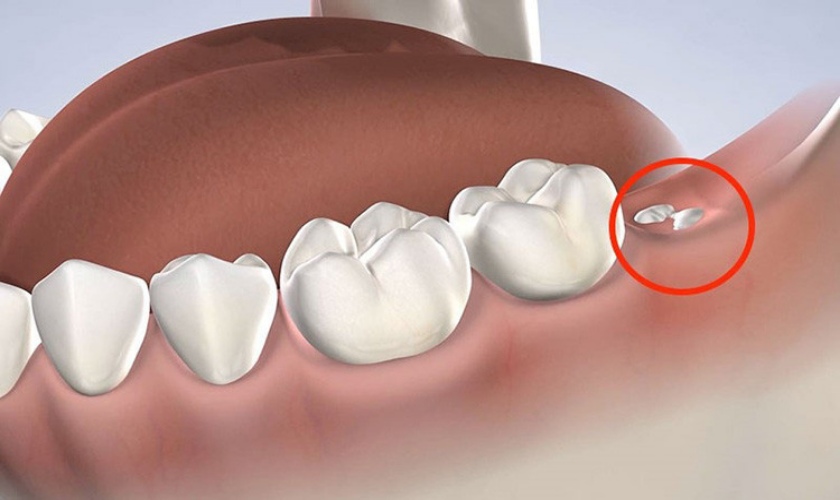

Nhổ răng khôn còn sót chân răng

Bác sĩ chủ động để lại chân răng để đảm bảo sức khỏe cho khách hàng

Một số trường hợp mối liên hệ giữa chân răng và các dây thần kinh quá gần nhau, nếu chân răng bị gãy trong quá trình nhổ sẽ rất khó lấy ra, nếu lấy ra phải phá huỷ xương của khách hàng rất nhiều.

Do đó, trong trường hợp này để đảm bảo an toàn cho khách hàng bác sĩ chủ động để lại và thông báo cho khách hàng biết.